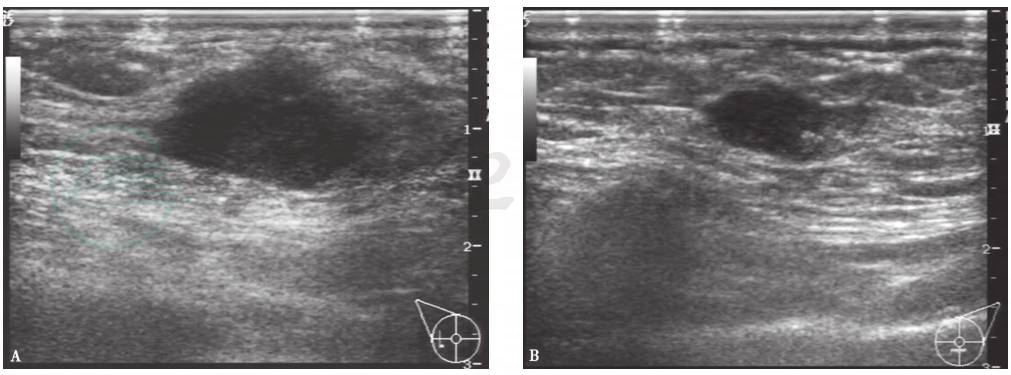

图1双侧乳腺癌超声

右侧乳腺外侧肿物呈低回声,形态不规整,边界不规则,呈蟹足样,后方回声衰减(A)。左侧乳腺中下方肿物,呈低回声,边缘不光滑(B)